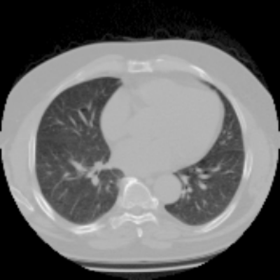

We now consider applying the proposed image registration method on real lung CT images retrieved from the National Lung Screening Trial (NLST) dataset [1]. Fig. 9(a) and Fig. 9(b) show two slices of lung CT images that we use as the source and the target (see Fig. 9(c) for the absolute intensity difference). We remark that the CT images are originally with different intensity, and so we apply an intensity histogram matching before running the registration experiment. Fig. 9(d) shows the registration result obtained by our proposed method. It can be observed that our method successfully produces a large deformation on the right lung of the source image to match that of the target image (see also Fig. 9(e) for the final absolute intensity difference). On the contrary, DDemons [47] (Fig. 9(f)), LDDMM [5] (Fig. 9(g)), Elastix [29] (Fig. 9(h)) and DROP [18] (Fig. 9(i)) all fail to produce an accurate and bijective registration result. This shows that our method is more capable of handling large deformation image registration.